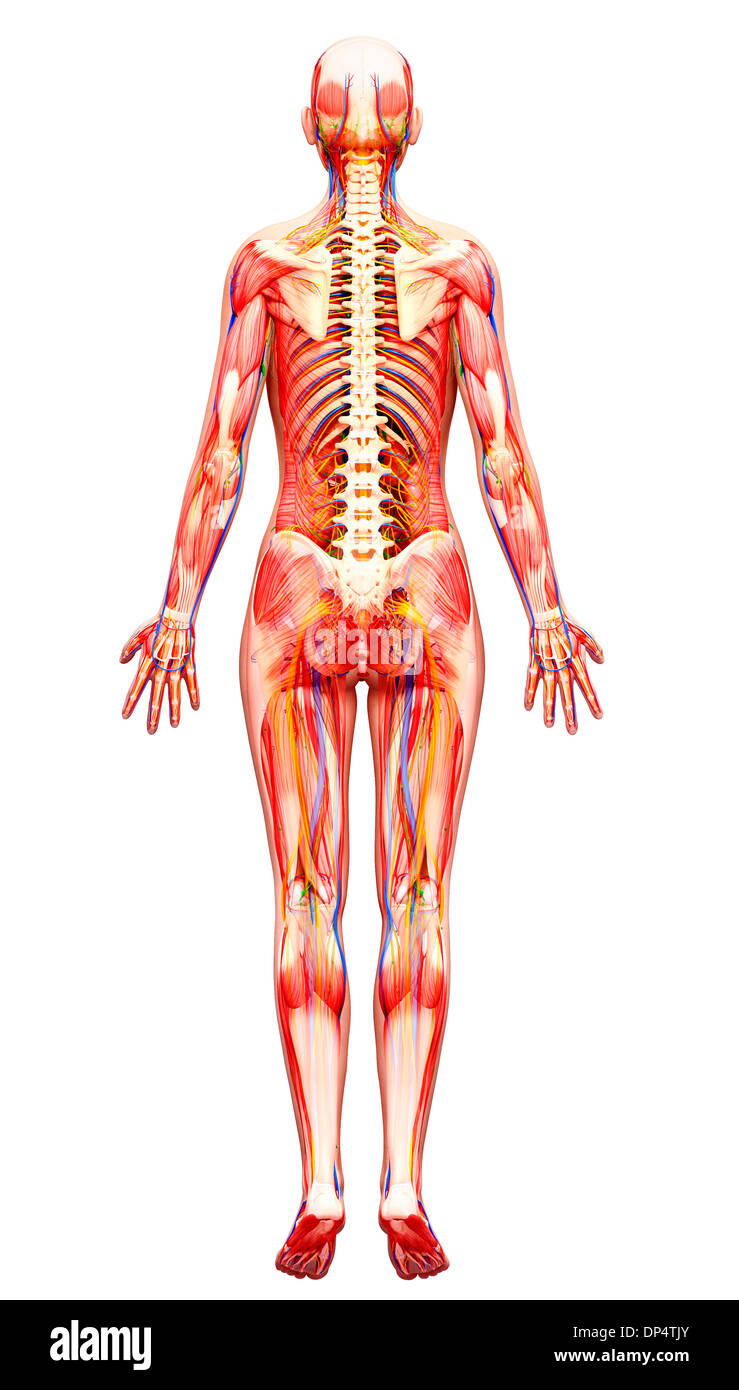

, Artwork Banque D'Imageshttps://www.alamyimages.fr/image-license-details/?v=1https://www.alamyimages.fr/artwork-image65260691.html

, Artwork Banque D'Imageshttps://www.alamyimages.fr/image-license-details/?v=1https://www.alamyimages.fr/artwork-image65260691.htmlRFDP4TJY–, Artwork